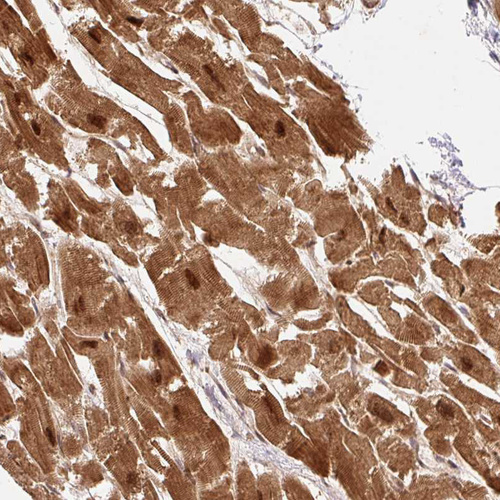

Immunohistochemical staining of human cerebral cortex, cervix, uterine, heart muscle and testis using Anti-PSMD1 antibody HPA036737 (A) shows similar protein distribution across tissues to independent antibody HPA036736 (B).